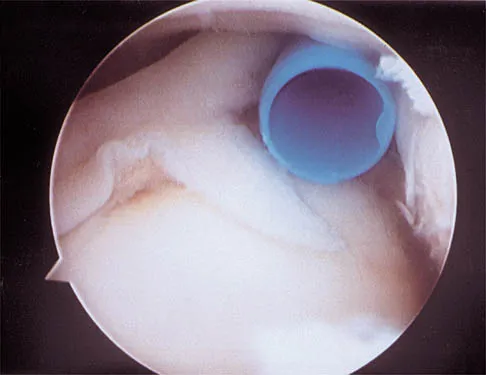

What neurovascular structure is in closest proximity to the probe in the arthroscopic view of the elbow shown in Figure 50?

Explanation